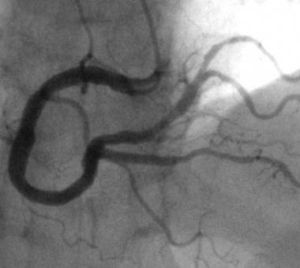

造影是一種常用的X線檢查方法。目前,儘管有了對組織器官分辨能力比普通X線強100倍的電子計算機X線斷層掃描(CT),但造影術仍不失為一種重要的輔助檢查方法。